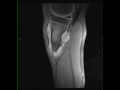

Periosteal Osteosarcoma Tibia

21-year-old male with pain in the proximal left leg. There is an infiltrative T1 hypointense lesion circumferentially extending along the medial cortical margin of the proximal left tibia. The hypointense signal extends into the medullary cavity of the proximal tibia. The lesion is STIR hyperintense and avidly enhances. Imaging findings are compatible with a periosteal osteosarcoma. Periosteal osteosarcoma is the second most common type of surface osteosarcoma after the parosteal subtype. Periosteal osteosarcoma arise from the inner germinative layer of periosteum. Lesions tend to be diaphyseal with the femur and tibia most commonly affected. The lesion arises from the cortical margin with intramedullary extension being rare.